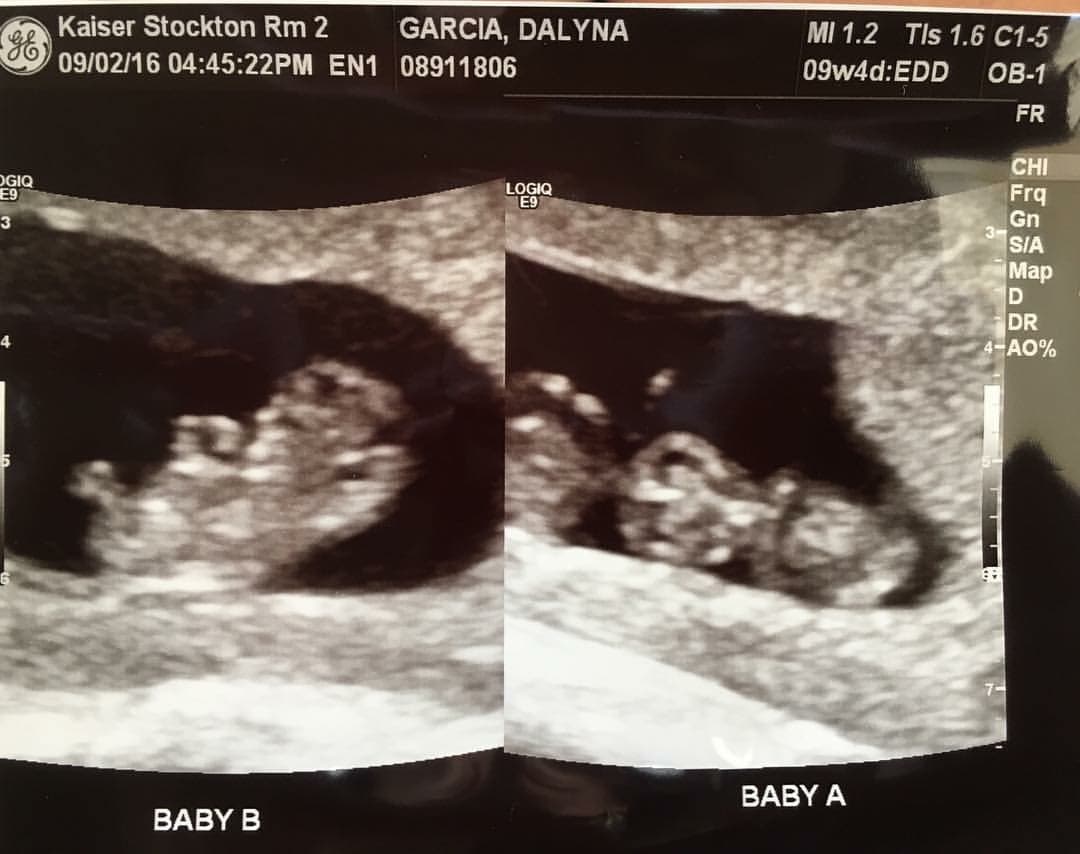

- Ultrasound Photos of 9 Weeks Pregnant With Twins

Ultrasound Photos of 9 Weeks Pregnant With Twins